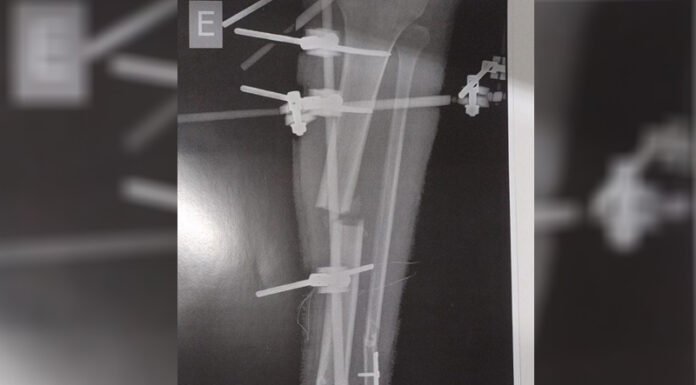

Uma mãe, que preferiu não se identificar, denunciou ao Boa Vista Já que sua filha de 20 anos está internada no Hospital Lotty Íris, aguardando há dois meses por uma cirurgia no fêmur. O motivo do atraso: um intensificador de imagem, equipamento altamente necessário para o procedimento, está quebrado e até agora não foi reparado nem substituído...

Familiares de um paciente, internado no Hospital Lotty Iris, denunciaram que aguardam por uma cirurgia há quatro meses. A denúncia foi feita nesta quarta-feira (12).

O paciente, identificado como Wilson Leitão Rodrigues, de 30 anos, está com dois fêmures fraturados e foi remanejado pela Secretaria de Estado da Saúde (Sesau) para a unidade particular....